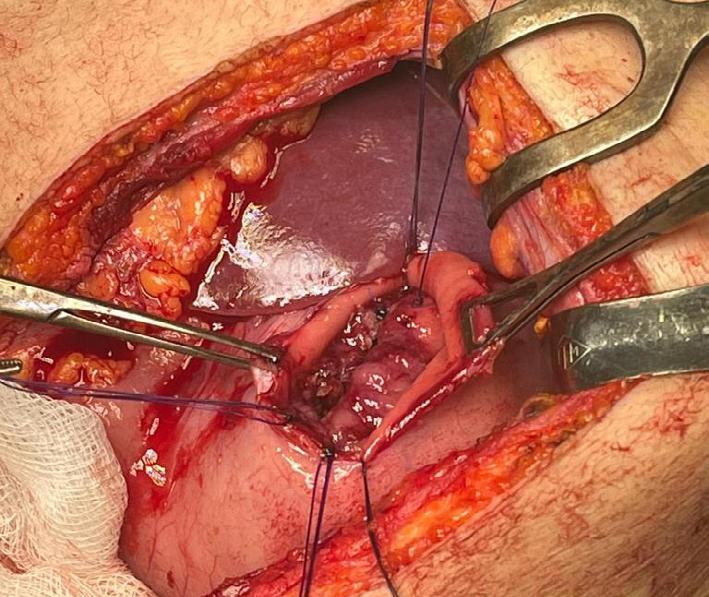

Caz 3 - Textilom

Pacientă în vârstă de 36 de ani, gravidă în luna a IX-a, se internează în cadrul secției de obstetrică-ginecologie în vederea nașterii prin operație cezariană, indicația fiind un uter cicatricial (intervenție obstetricală anterioară). Se practică operație cezariană segmentară transversă, însă intraoperator apar fenomene hemoragice importante, motiv pentru care se impune efectuarea unei histerectomii totale.

Evoluția postoperatorie este lent favorabilă, cu apariția durerilor abdominale

persistente, absența reluării tranzitului intestinal și o deteriorare progresivă a stării generale. În contextul acestor manifestări, se efectuează o ecografie abdominală, care evidențiază o formațiune pelvină sugestivă pentru retenție de corp străin.

Se decide efectuarea unei laparoscopii exploratorii, în cursul căreia se identifică și se extrage un textilom intraabdominal. Se montează drenaj peritoneal. Evoluția postoperatorie ulterioară este favorabilă, cu ameliorarea simptomatologiei și reluarea progresivă a tranzitului intestinal.